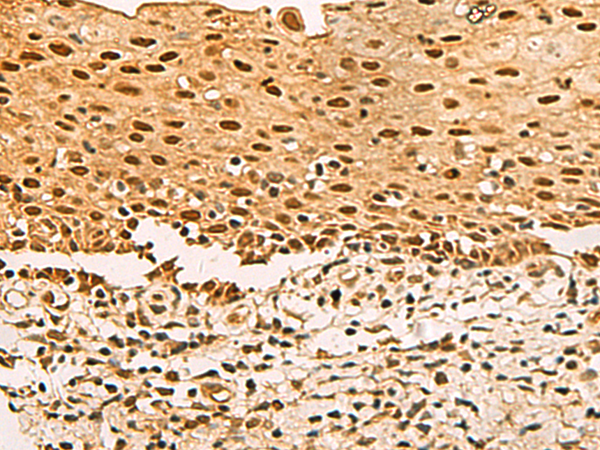

分类: 科研抗体货号: P08972别名: PHM27应用: IHC反应种属: Human, Rat